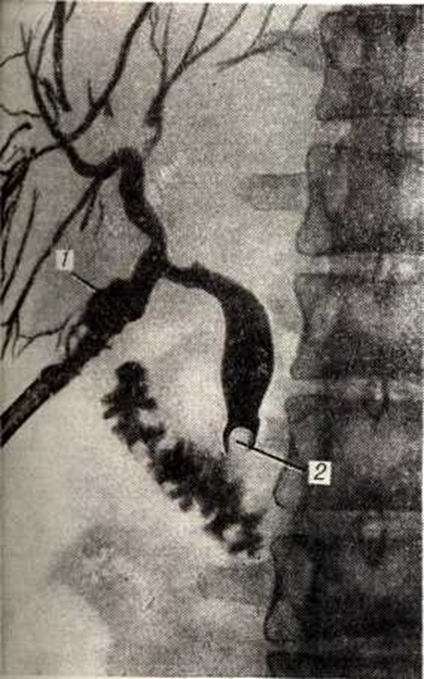

Диагноз наружного Жёлчные свищи обычно устанавливается без труда на основании истечения из свища желчи (смотри полный свод знаний), однако определить с достоверностью, откуда исходит свищ, удаётся после рентгенологическое исследования (рисунок 1). Одним из самых простых и информативных методов является фистулография (смотри полный свод знаний), позволяющая получить ценные данные.